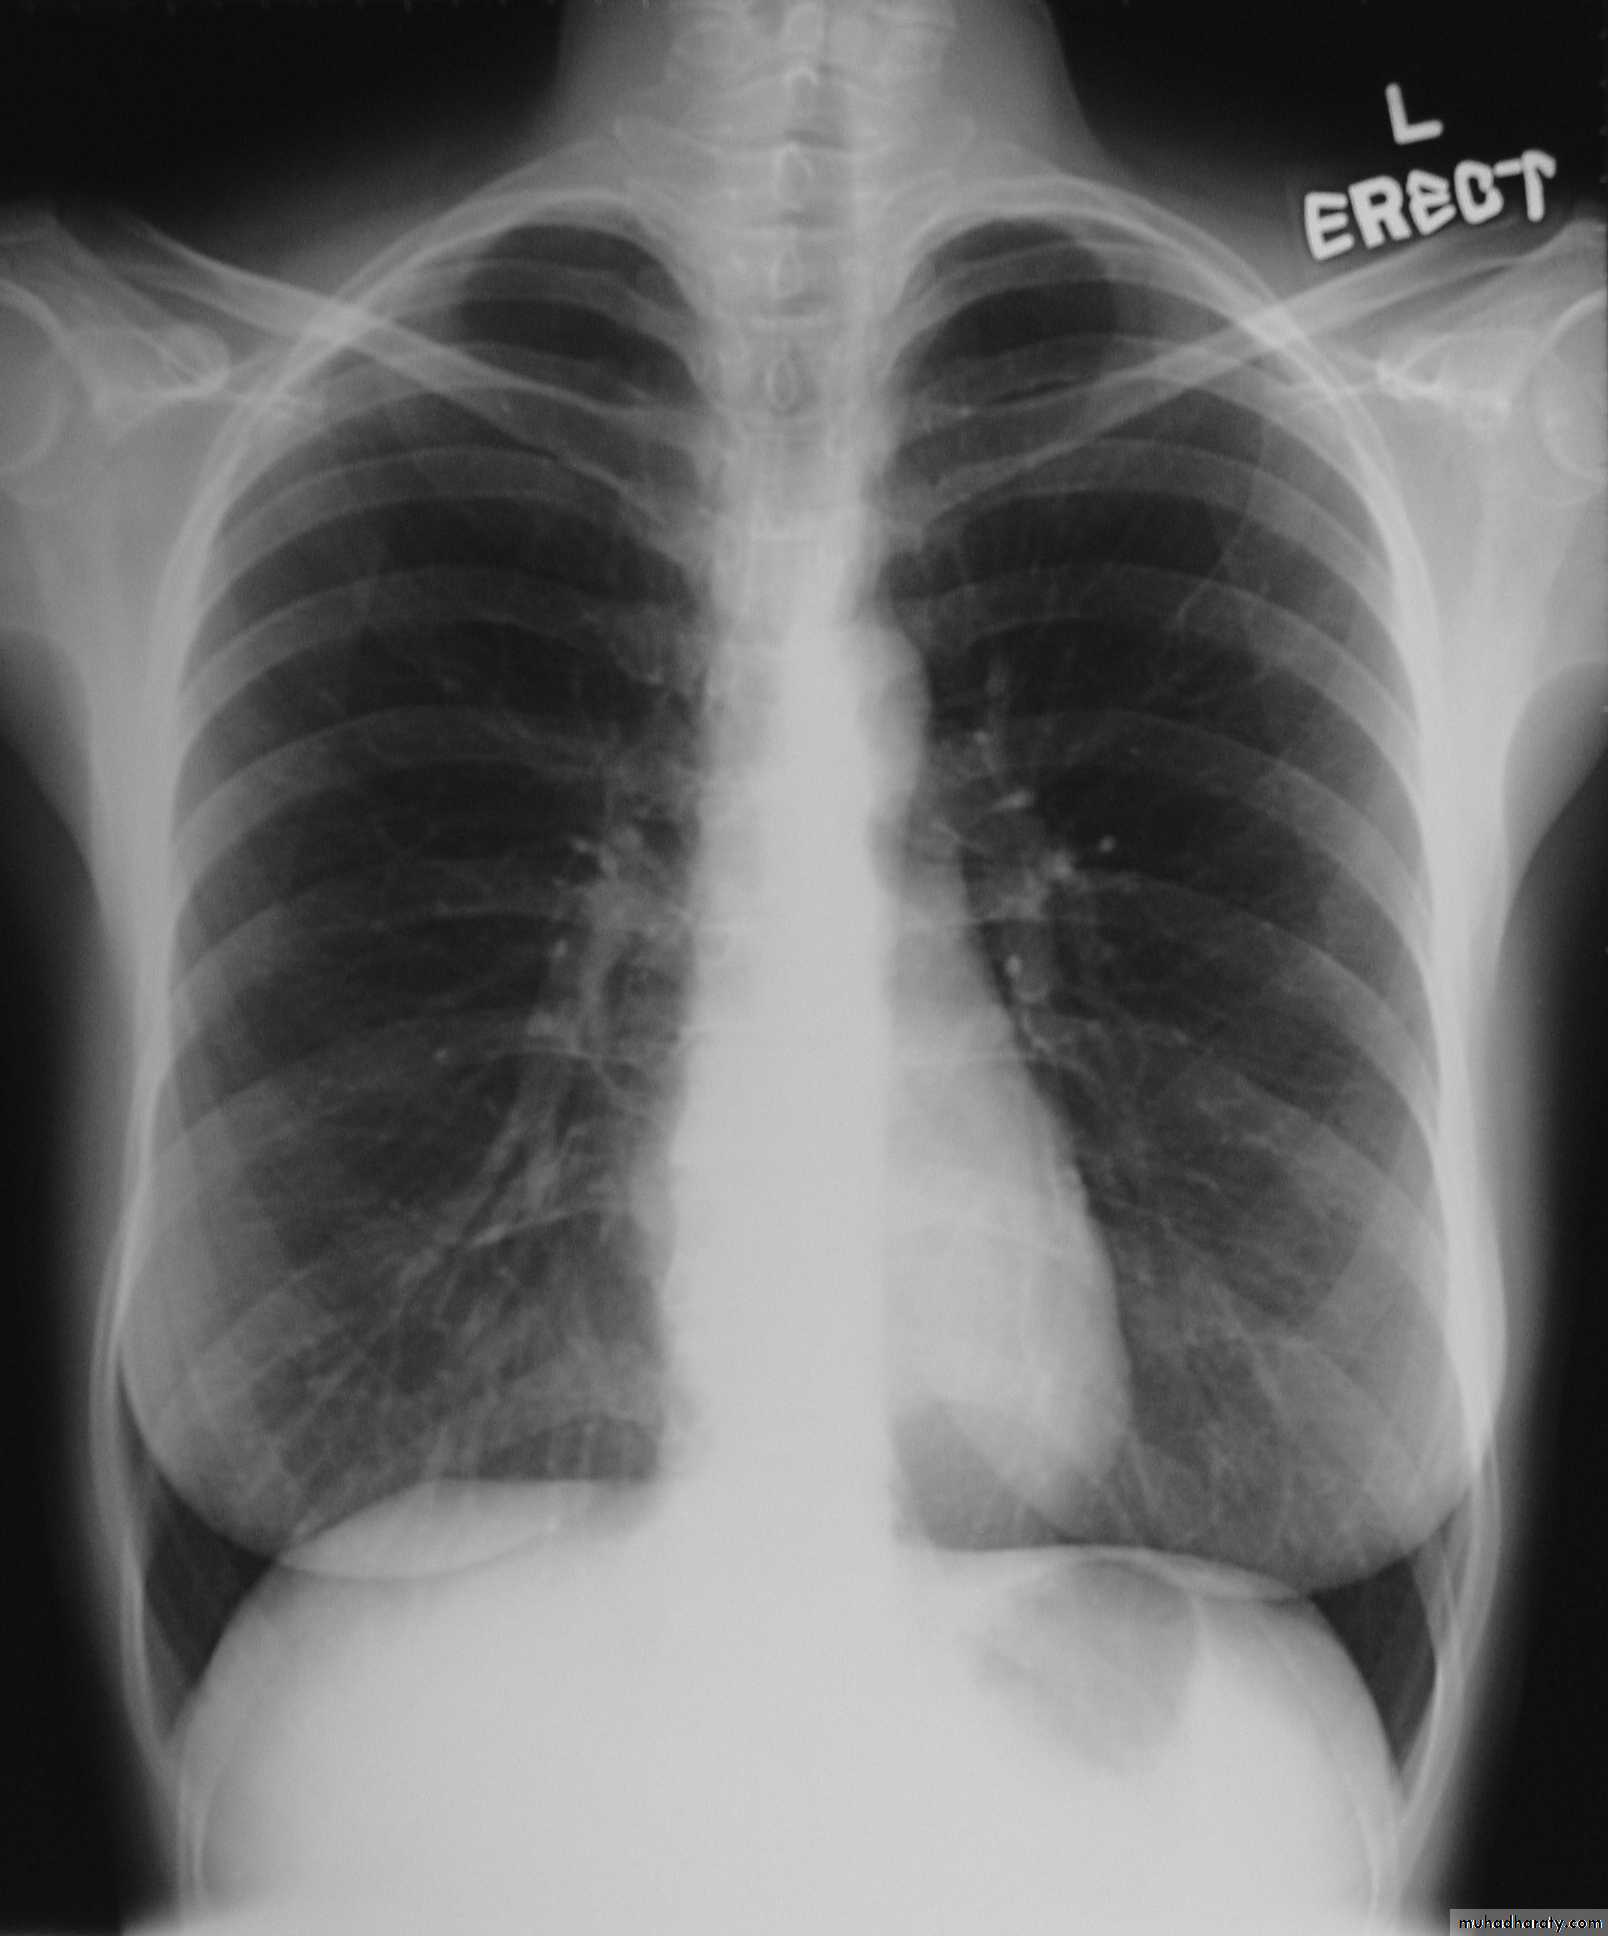

Radiology

Chest X-ray: typically small lung volumes with reticulonodular shadowing

Abnormal chest X-ray at presentation with lower zone bi-basal reticular and reticulonodular opacities. 'honeycomb' appearance in advanced disease.